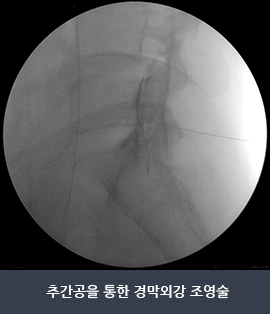

- 증상의 완화를 위해 디스크와 신경막 사이에 주사를 하는 경막외강 주사를 시행합니다.